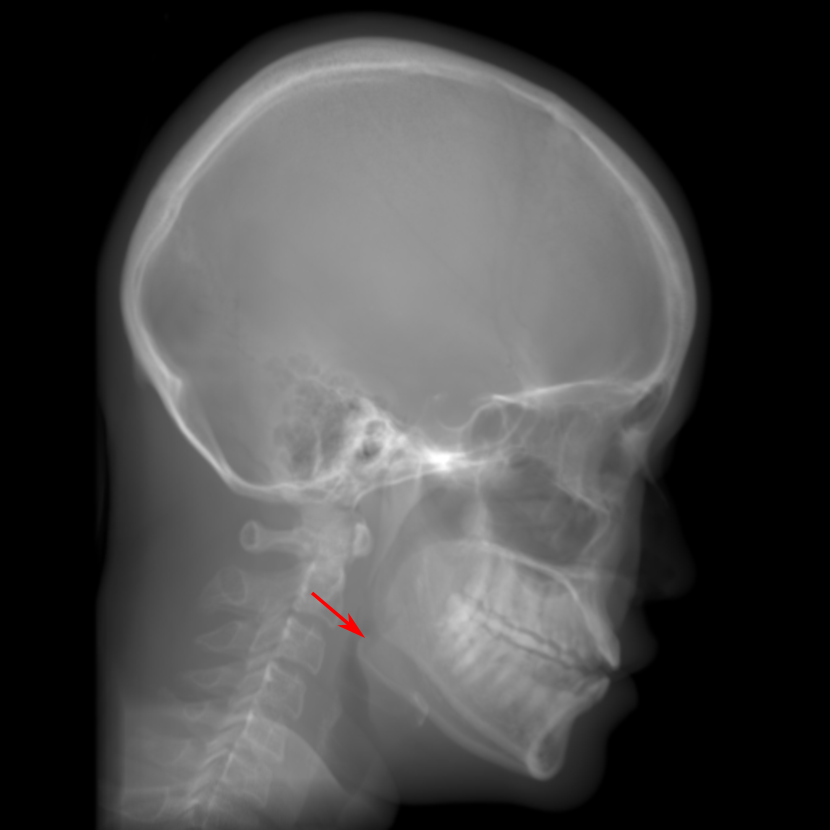

5.2 Head Data

Refer to caption

(a) Reference

(b) 0superscript00^{\circ} perspective

(c) (b)-(a)

7.80, 0.9093

Pix2pixGAN Prediction

(d) 0superscript00^{\circ} Cartesian

(e) 0&180superscript0superscript1800^{\circ}\&180^{\circ} Cartesian

(f) 0&180superscript0superscript1800^{\circ}\&180^{\circ} polar

6.06, 0.9249

2.99, 0.9820

2.07, 0.9842

Pix2pixGAN difference

(g) (d)-(a)

(h) (e)-(a)

(i) (f)-(a)

TransU-Net Prediction

(j) 0superscript00^{\circ} Cartesian

(k) 0&180superscript0superscript1800^{\circ}\&180^{\circ} Cartesian

(l) 0&180superscript0superscript1800^{\circ}\&180^{\circ} polar

6.45, 0.9356

2.36, 0.9864

3.65, 0.9734

TransU-Net Difference

(m) (j)-(a)

(n) (k)-(a)

(o) (l)-(a)

Figure 11: Perspective deformation learning in one exemplary patient case for cephalometric imaging. In (b), the left and right sides of the mandible do not overlap well, as indicated by the arrow. In (c), a scale bar of 2 mm is displayed (zoom in for better visualization), as 2 mm is the clinically acceptable precision for cephalometric landmark detection. In (e), (h) and (j), incorrect areas are marked by the red arrows.

The results of one exemplary patient for cephalometric imaging are displayed in Fig. 11. In the 0superscript00^{\circ} perspective projection image (Fig. 11(b)), because of perspective deformation, anatomical structures from the left and right sides do not overlap well, especially for the mandible as indicated by the red arrow in Fig. 11(b). It causes inaccuracy in determining the cephalometric landmark of the gonion. The difference of Fig. 11(b) to the reference Fig. 11(a) is displayed in Fig. 11(c). A scale bar of 2 mm is displayed in Fig. 11(c), as 2 mm is the clinically acceptable precision for cephalometric landmark detection. It is obvious that many anatomical structures in the 0superscript00^{\circ} perspective projection images have position shifts larger than 2 mm. In the prediction image (Fig. 11(d)) using a single 0superscript00^{\circ} view in Cartesian coordinates, perspective deformation is reduced to some degree, as displayed in the difference image Fig. 11(g). For example, the mandible region has less error. However, Fig. 11(g) also indicates that many bony structures still have deviations larger than 2 mm. The results of learning from dual complementary views in Cartesian and polar coordinates are displayed in Fig. 11(e) and Fig. 11(f), respectively. Both images have little perspective deformation, as revealed by their difference images in Fig. 11(h) and Fig. 11(i). Nevertheless, in Fig. 11(e), two dark regions are indicated by the two arrows, which are better visualized in the difference image Fig. 11(h). The results of TransU-Net are displayed in Figs. 11(j)-(o). In Fig. 11(m), the structures near the porion landmark are distorted, for example, the ear canal indicated by the arrow. Consistent with Pix2pixGAN, perspective deformation is largely reduced in the both TransU-Net prediction images using dual complementary views in Cartesian and polar coordinates.